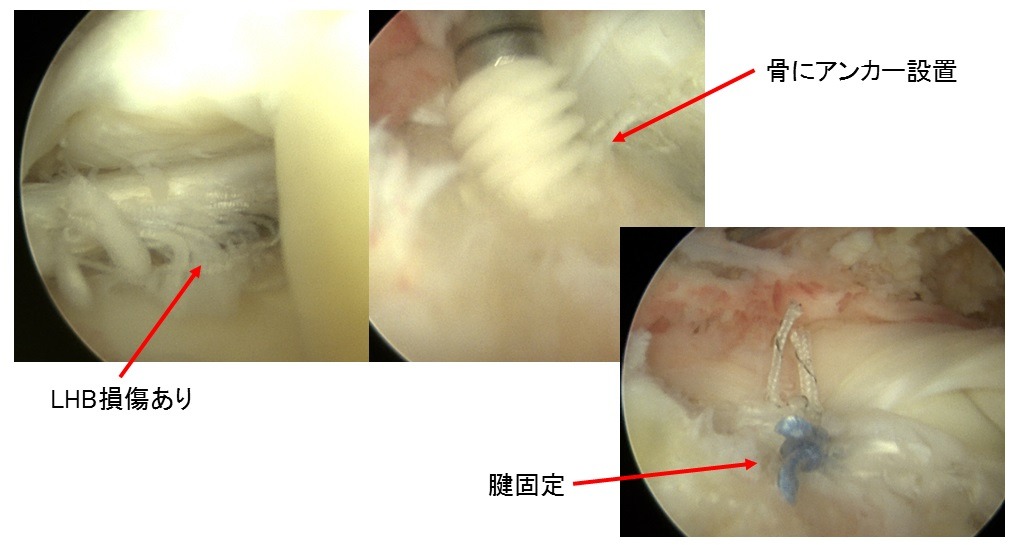

- 上腕二頭筋腱長頭(LHB)固定もしくは切除:必要に応じてLHBの処置を行います。

⑤上腕二頭筋長頭筋腱(LHB)の腱固定

③腱板縫合

U字型の中断裂

上腕骨頭(大結節Footprint)が露出してしまっている。

内側アンカー設置

吸収性アンカー(直径4.5から5.5mm)

器具を使用して腱板に糸をかける

外側アンカー設置

Suture-bridge完成

露出していた骨頭は見えなくなり、腱板で覆われています。